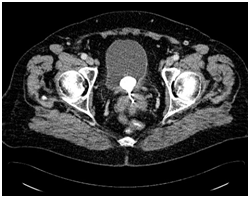

At this point vaginal examination was done- vagina was closed 2 cm proximal to the vaginal introitus and no cervix was visualised. Vaginal smear was taken for cytological analysis which was negative for intraepithelial neoplasia. There was no clear outline of the uterus and ovaries visible on transrectal ultrasonography. IUD was not visualised and there was no fluid in the Pouch of Douglas. Transabdominal ultrasound showed intravesical hyperechoic reflection 3.4 cm in diameter which could represent stone. Further pelvic and abdominal CT scan revealed hyperdense linear formation with dimensions of 2.9x 5.0 cm placed in the uterine isthmus and vagina that descends to the introitus of the vagina. Furthermore, round calcified formation with dimensions of 3.0x2.4 cm was revealed in the posterior bladder wall (Figure 1). These two formations were in close contact.

Figure 1 Pelvic computed tomography shows 3.0x 2.4 cm – sized bladder calculus in close contact with the IUD placed in the vaginal fornix.